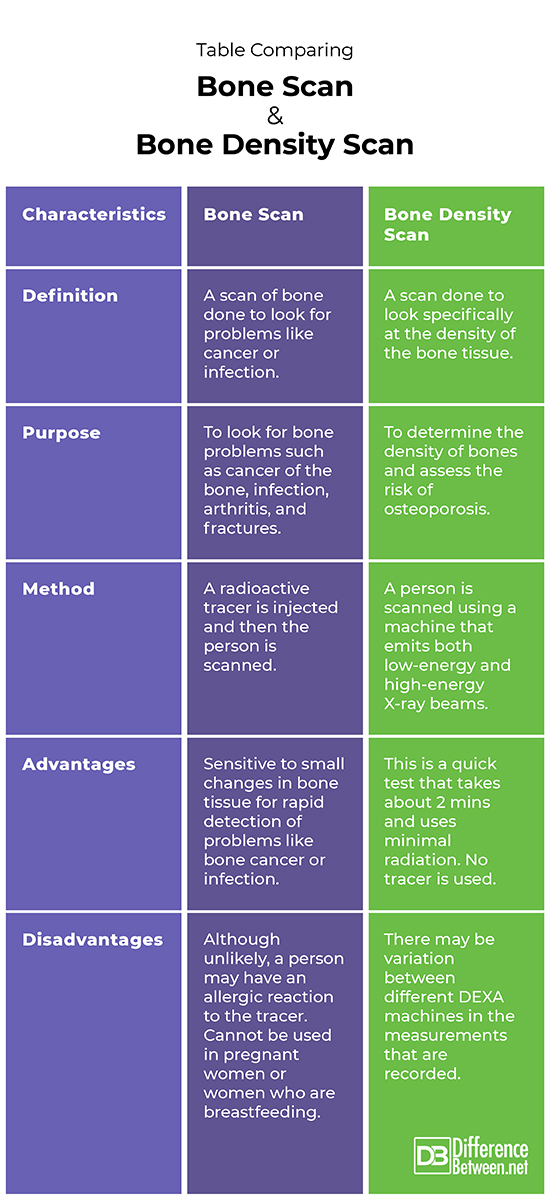

Definition

A bone scan is a scan of bone to look for problems like cancer or infection. A bone density scan is imaging done to look at the density of the bone.

Purpose

The purpose of a bone scan is to check for problems like infection and cancer. The purpose of a bone density scan is to look at the density of bone and assess the risk of osteoporosis.

Method

With a bone scan, a radioactive tracer is injected into the person and then the scan done. With a bone density scan, both low-energy and high-energy X-ray beams are used.

Advantages

A bone scan is sensitive to even small changes in bone tissue that can allow rapid detection of problems like bone cancer or infection. A bone density scan is quick and does not use radioactive tracers.

Disadvantages

A drawback of a bone scan is it uses radioactive tracers that people may be allergic to. A drawback of a bone density scan is that DEXA machines are not all standardized.

Table comparing Bone Scan and Bone Density Scan